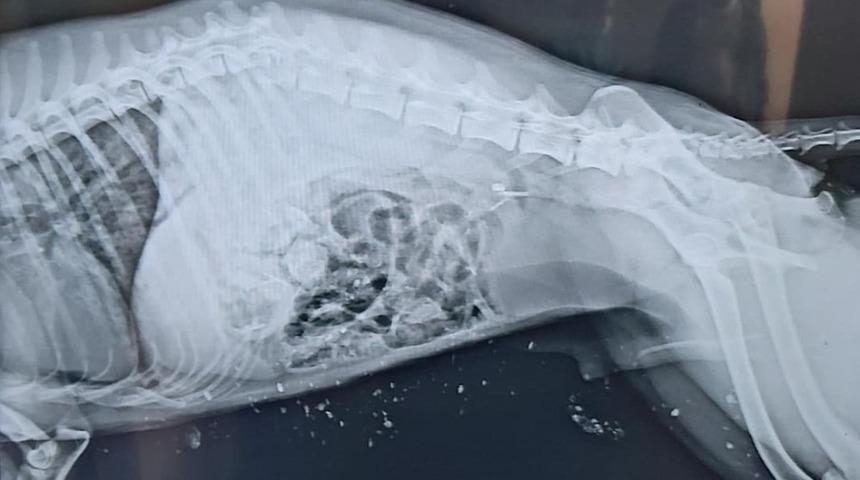

Edinilen bilgilere göre, Iğdır merkezde otoyol üzerinde bir aracın çarpması sonucu yaralanan Çakal’ı gören vatandaşlar ekiplere haber verdi. Haber verilmesi üzerine olay yerine gelen ekipler, ağır yaralı Çakal’a ilk müdahalesini yaparak hayvan barınağına götürdü. Daha sonra, Kafkas Üniversitesi Veteriner Fakültesi Hayvan Hastanesi Kliniğinde yapılan radyolojik muayenede, Çakal’ın omuriliğinin kırıldığı, ön bacaklarında parçalı kırık ve kanama olduğu, bu bulgulara bağlı olarak arka bacaklarının tutmadığı tespit edildi. Ağır yaralanan Çakal, Kafkas Üniversitesi Veterinerlik Fakültesi Hayvan Hastanesi’nde tedavi altına alındığı öğrenildi.